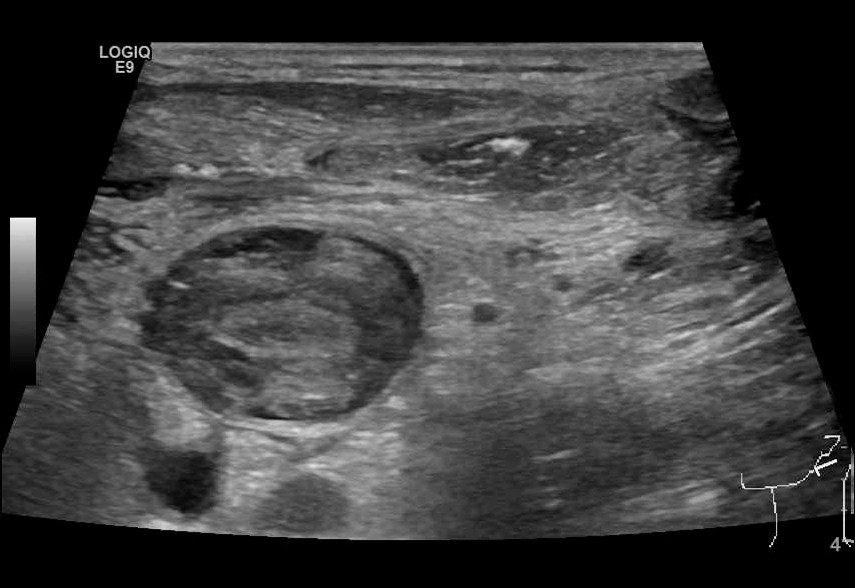

Ultralydundersøkelsen av halsen viste imidlertid en betydelig trombemasse som nærmest totalokkluderte venstre v. jugularis interna og v. subclavia (figur 1 og 2). Den totale utbredelsen av tromben kunne ikke fremstilles med ultralyd, og det ble derfor supplert med en CT-venografi, som viste utbredt trombosering som omfattet nedre del av venstre v. jugularis (fra nivå med carotisbifurkaturen), v. subclavia og v. brachiocephalica frem til innløpet av v. cava superior (figur 3). Det var multiple luftbobler fordelt i trombemassen. Vi mistenkte at dette var forårsaket av bakterier, og dermed at en infisert trombe var fokus for pasientens infeksjon.

Ultralyd er en ikke-invasiv og kostnadseffektiv metode for å påvise trombemasser. Dessverre er den suboptimal for diagnostikk av tromber lokalisert dypt under mandibula eller clavicula. CT-venografi er derfor av mange anbefalt som foretrukket undersøkelsesmetode (6). I vårt tilfelle fikk vi med CT-venografi identifisert hele utbredelsen av trombemassen samt påvist karakteristiske luftbobler som underbygget mistanken om infisert trombe.